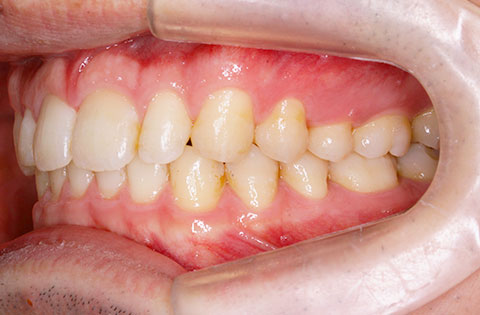

矯正前

矯正前 正面

矯正前 右側

矯正前 左側

主訴 正中が開いている。咬み合わせが深く歯肉を咬んでしまう。

年齢 20代

治療法 上下顎マルチブラケット装置

抜歯の有無 なし

治療期間 1年6ヶ月